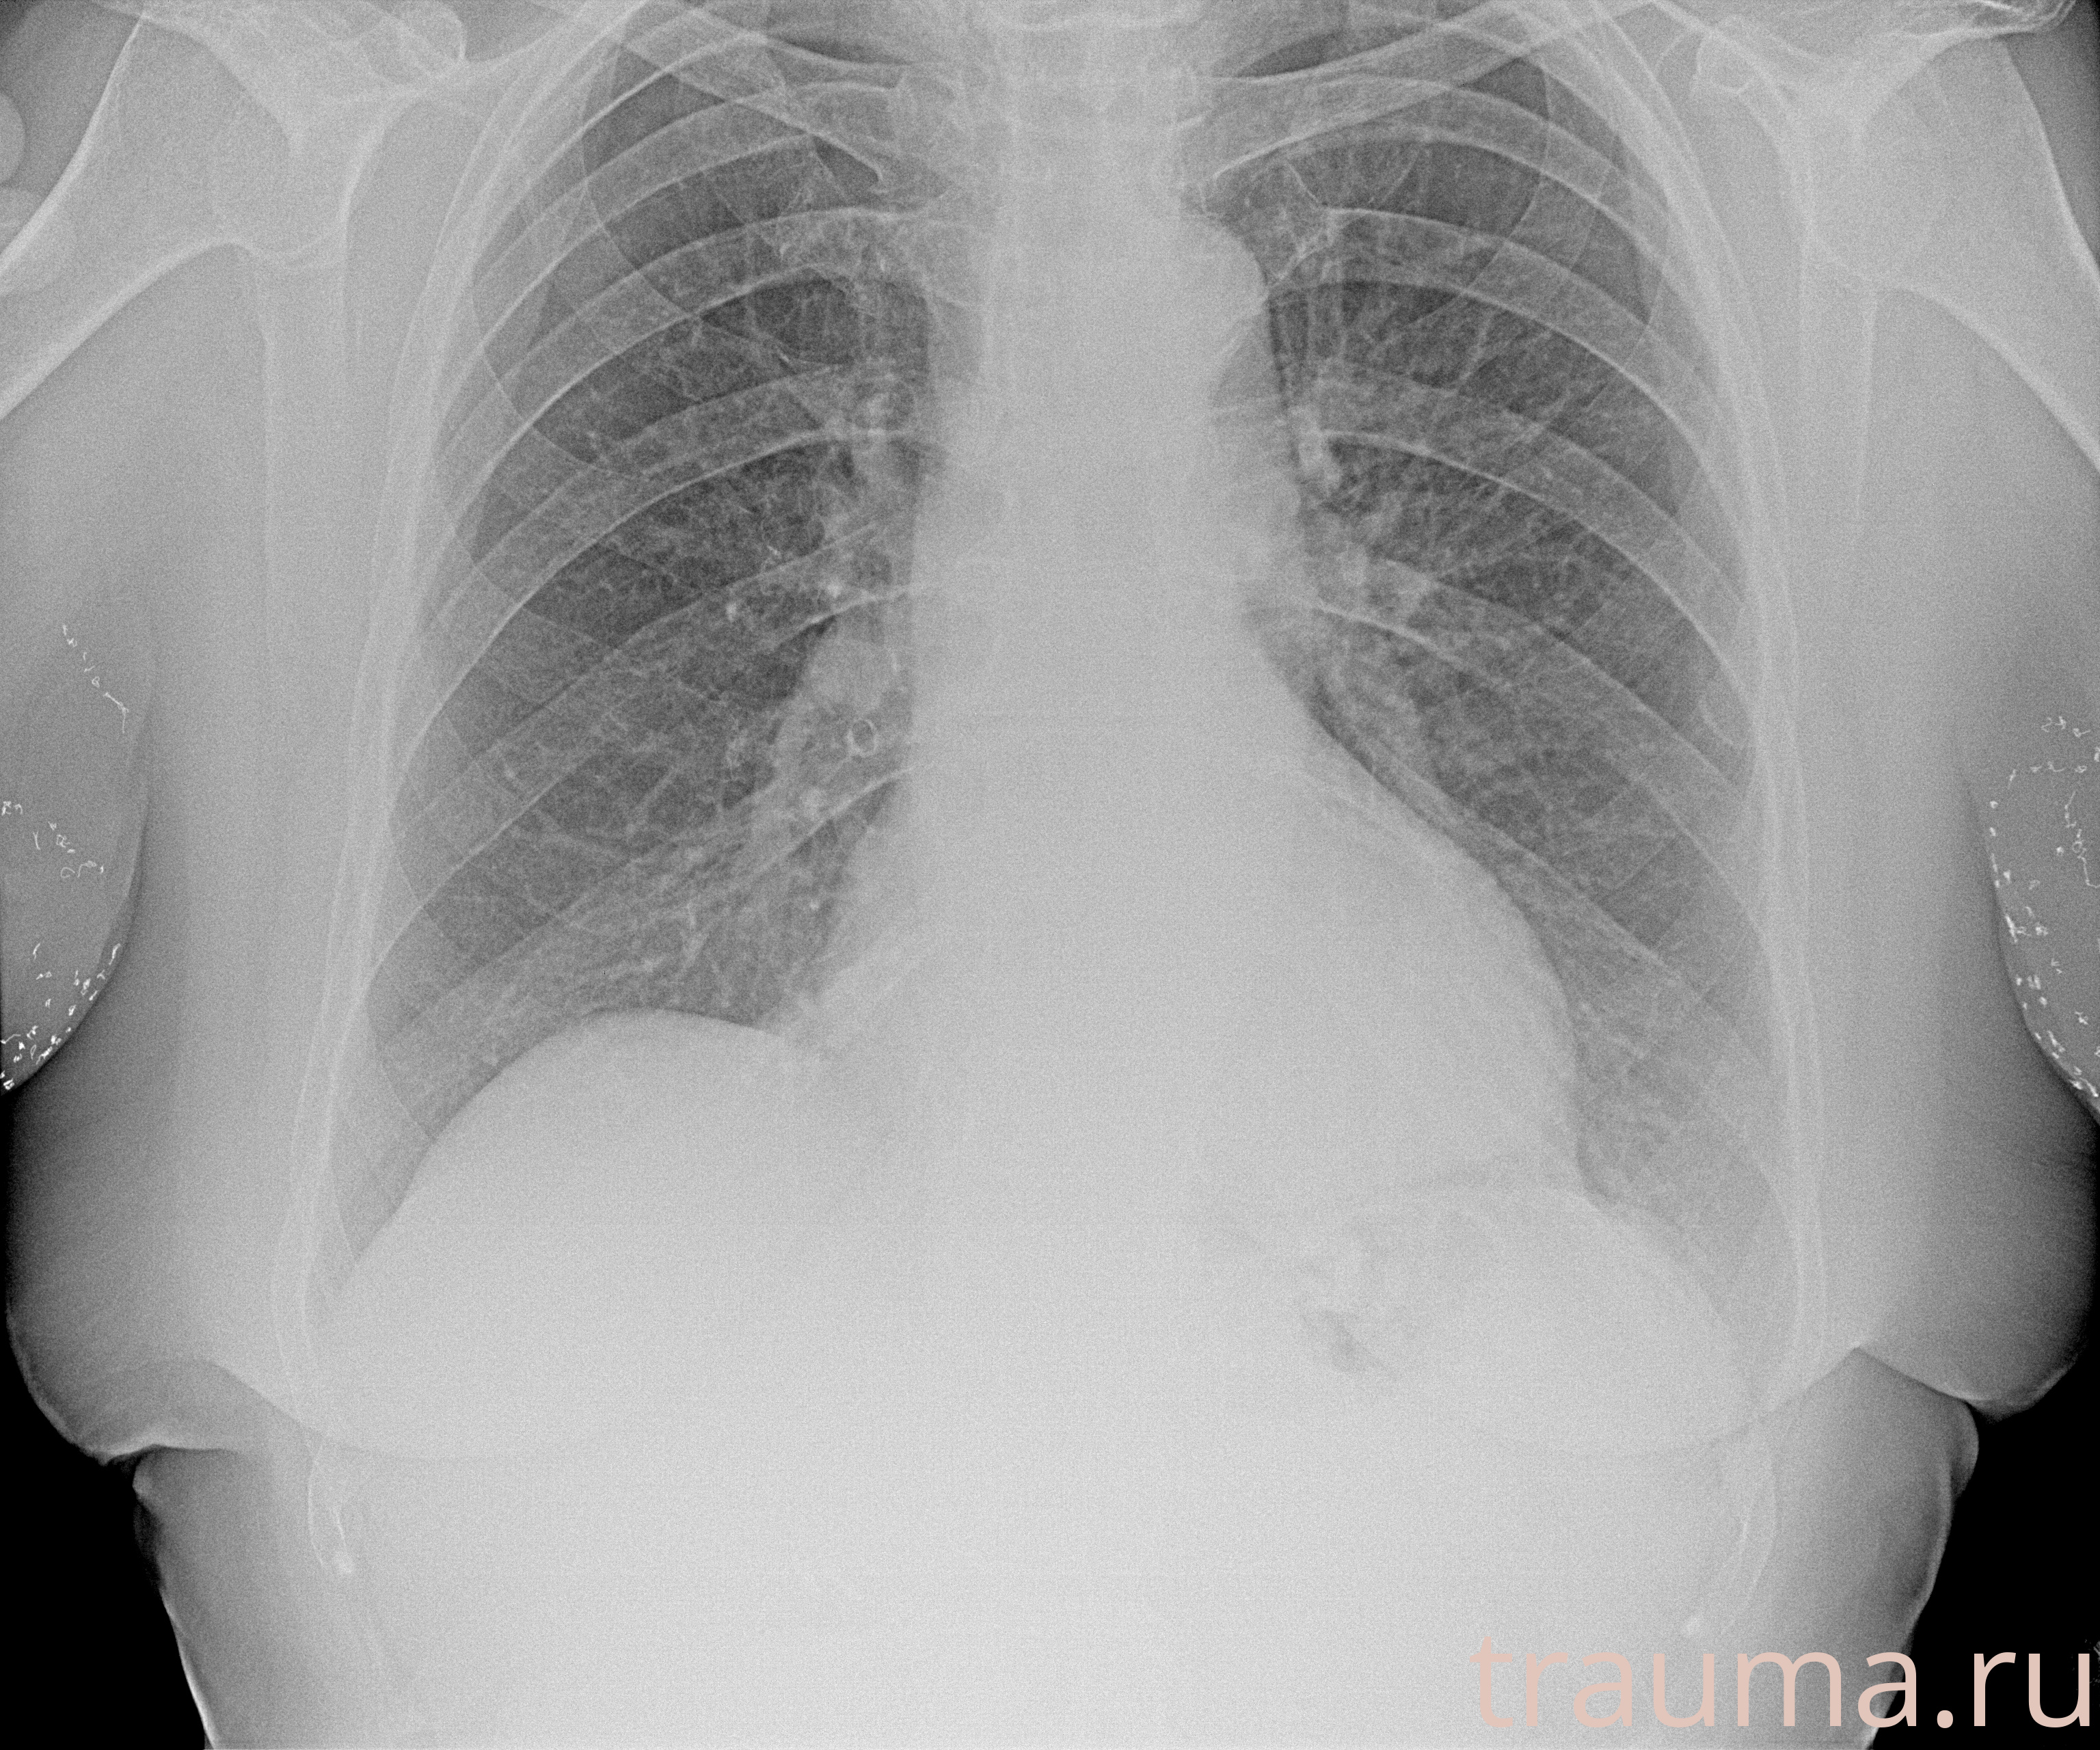

Рентген на дому: по вашему адресу приезжает врач-рентгенолог, травматолог-ортопед с мобильным рентгеновским аппаратом, проводит диагностику травмы или заболевания, делает необходимые рентгенограммы, дает рекомендации по дальнейшему лечению. Получить качественные снимки в домашних условиях возможно благодаря уникальной методике, разработанной МосРентген Центром для института  Склифосовского

при переломе шейки бедра и пневмонии от компании МосРентген Центр - партнера Института имени Склифосовского